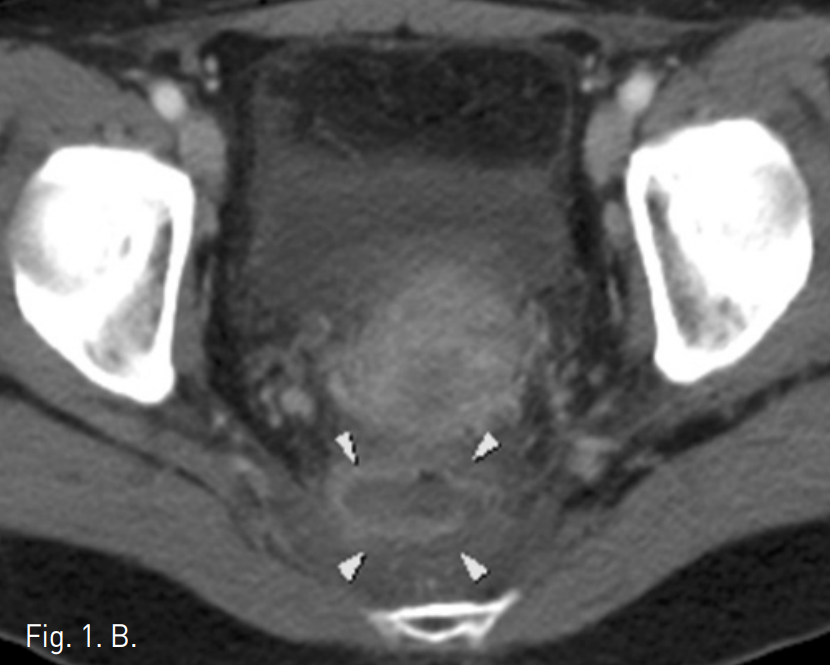

Fig. 2

A, B. 18G Chiba needle was inserted into presacral abscess by fluoroscopic and US-guided transgluteal approach. After injection of contrast media, 8.5F catheter was successfully inserted in to the lesion.